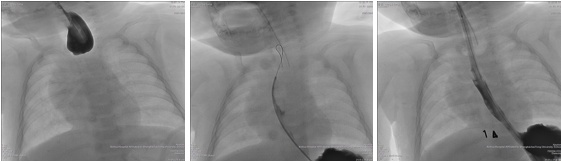

王俊主任组织多学科会诊,为小亨利制定精细化诊疗方案。介入血管外科俞炬明主任与儿普外科邬文杰副主任强强联合,对小亨利实施DSA引导下食管造影检查,明确核心病灶点——食管近段闭锁程度极高,造影剂完全无法通行。(A图)

面对疑难病情,团队摒弃传统路径,创新采用“自食管远段向近段逆行置入导引导丝”技术:从胃造瘘口入径,经食管下段逆行造影,启用超细微导丝在影像引导下探查食管细微开口。(B图)这一操作需要极致耐心与毫厘不差的操作精度,稍有失误可能引发食管穿孔。

团队历经精细探查,成功定位食管隐匿开口,并顺利将4mm球囊导管置入闭锁食管段,通过球囊扩张打通食管通路。(C图)整场手术创伤极小,却精准破解了原本需二次开胸才能解决的难题。

以上图为DSA造影检查(A、近端食管几乎完全闭锁,造影剂无法通过;B、自食管远端逆行置入导丝;C、导丝引导下置入食道球囊,扩开食道)